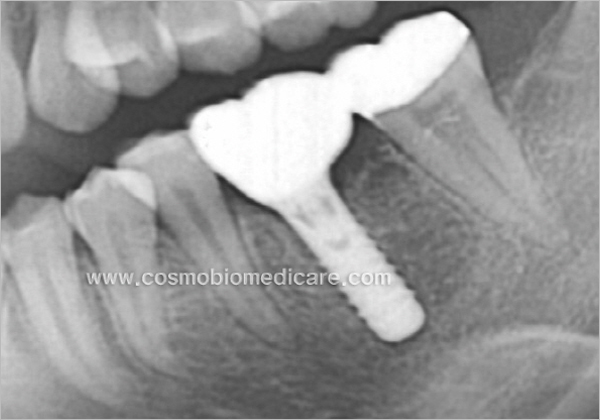

Clinical Cases

• Case1